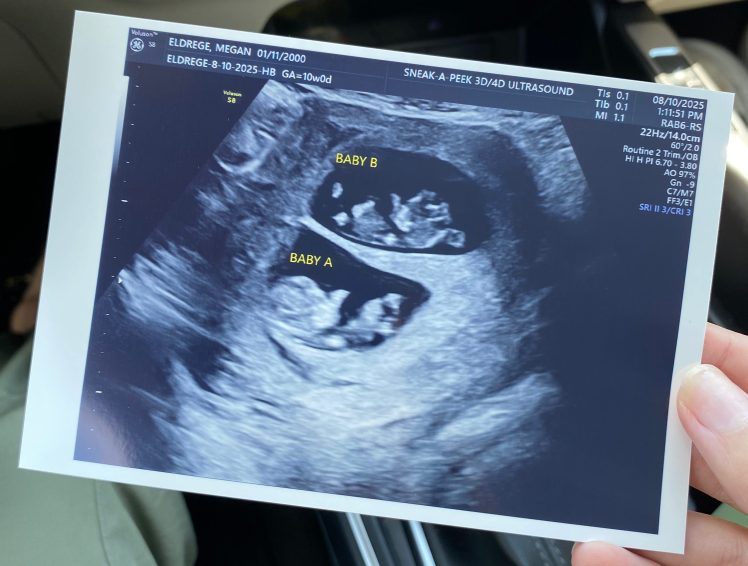

We are over the moon to be expecting two new babies, but nothing could have prepared me for how hard pregnancy after loss would be.

And so this went on, every week. Scans and appointments temporarily eased my anxiety about losing my babies, but then I would find some new reason to be stressed and the cycle started over again. I am lucky that I am pregnant with twins and receive far more ultrasounds than normal, but that doesn’t change the fact that no amount of tests and scans can fully alleviate the uncertainty and anxiety that tends to haunt a pregnancy after a loss.

Anyone who has experienced pregnancy after loss knows all too well that a rainbow baby does not fix the heartbreak. Children cannot replace children, and the grief from losing a pregnancy lives in your heart forever. But through it all, I can’t help but feel grateful when I picture my two angel babies in heaven sending me two more rainbow babies to love. This pregnancy hasn’t been what I thought it would be in many ways, but I cannot wait until I can snuggle two tiny newborns at the same time and take solace in knowing that everything worked out exactly as God intended.